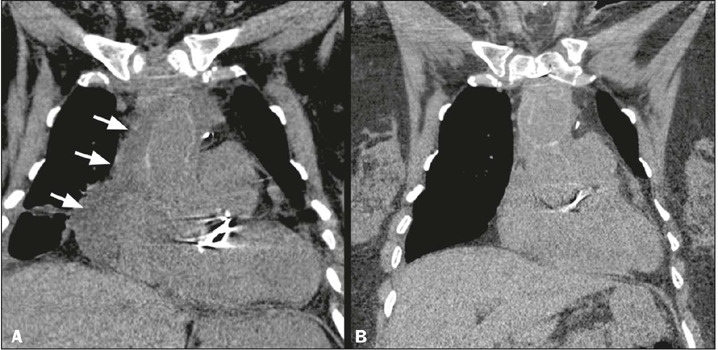

A typical approach for many cardiovascular surgical procedures is median sternotomy. Despite advances in surgical techniques and postoperative care, complications still occur in 0.5-5.0% of cases. Radiological assessment of the chest after sternotomy is a challenge, because normal findings resulting from surgical trauma can resemble complications. This pictorial essay aims to provide an overview of normal postoperative imaging findings and the spectrum of complications that can arise, including surgical material-related issues, hematomas, bone complications, and infections. Diagnosis and management require careful interpretation of imaging studies, considering the recovery timeline and clinical status of the patient. With the increasing number of cardiothoracic surgical procedures, this is essential knowledge for radiologists, allowing them to contribute to an accurate diagnosis and the appropriate management of patients.